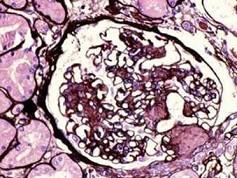

阅读下述三张狼疮性肾炎病理图片后,其病理诊断为 ( )A.Ⅲ型LNB.Ⅰ型LNC.Ⅳ型LND.Ⅴ型LNE.Ⅱ型LN

选项 A.Ⅲ型LN B.Ⅰ型LN C.Ⅳ型LN D.Ⅴ型LN E.Ⅱ型LN

答案 D